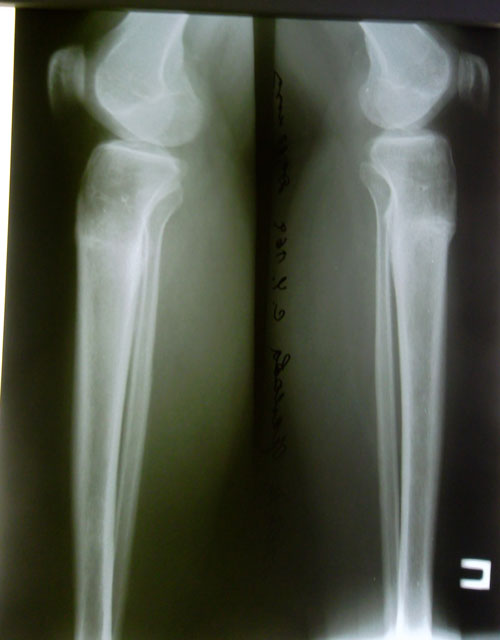

рентген в 76 дней.

Сращение отличное, предполагаемая дата снятия аппаратов - 06 января 2014г.

Рентген в 2 месяца после снятия аппаратов.

Разрешено всё без ограничений!